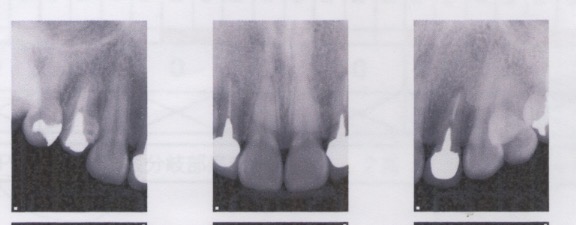

矯正治療を行なったにも関わらず、上顎左右側の側切歯の歯肉ラインが揃っていません。

上顎左右側の側切歯の補綴装置が矯正治療以前のままです。

矯正前に補綴装置のやり直しを前提に矯正を行うべきと考えます。

補綴装置のやり直しなしで歯肉ラインを揃えるには、上顎左右側の側切歯を圧下することになります。

しかし、切端は揃わなくなります。つまり、短い歯になってしまいます。

結局、歯の圧下を行い歯肉ラインを揃えて、補綴のやり直しを行う治療が必要でした。

この患者さんの場合は、余った上顎左右側の側切歯の歯肉を除去することで対応します。

やる必要のなかった歯周外科を行う結果となりました。

- 歯周外科の後、上顎前歯3本のラミネートベニア、4本のオールセラミッククラウンを装着した。

Periodontal surgery

Gum level Periodontal surgery Ceramic